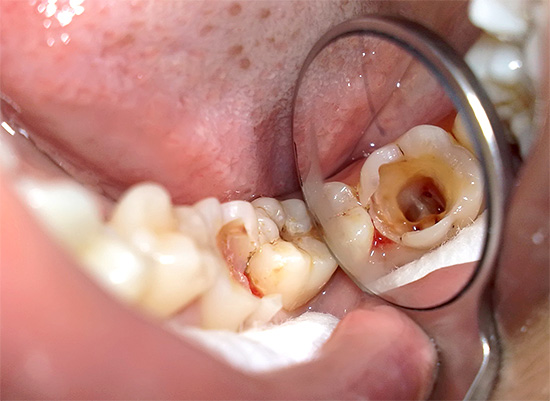

La foto sotto mostra un dente in cui la carie profonda ha portato allo sviluppo della pulpite:

Molte persone conoscono in prima persona la possibile comparsa del cosiddetto "flusso" (periostite). Ma poche persone sanno che il flusso sulla gomma appare spesso dopo un prolungato dolore alla polpite ed è il risultato della morte del "nervo" nel canale dentale con la formazione di pus, che semplicemente non ha nessun posto dove andare, e quindi va al lato della radice del dente, gonfiando la gomma.